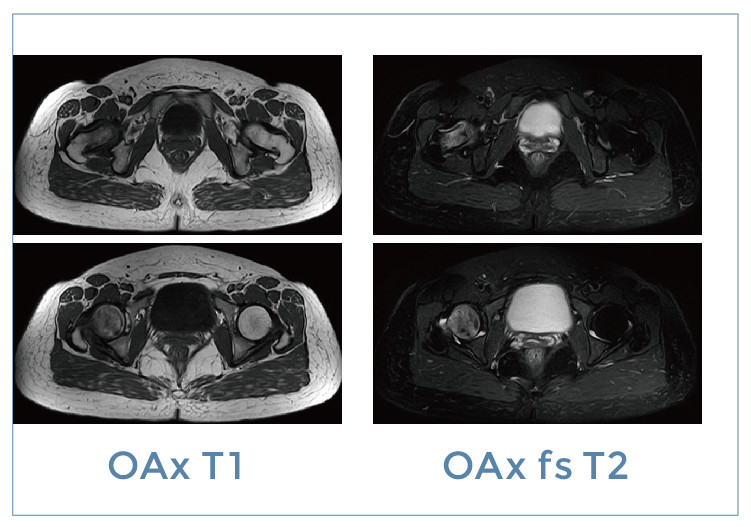

【朗润影像档案】磁共振影像病例分享(编号20191129)